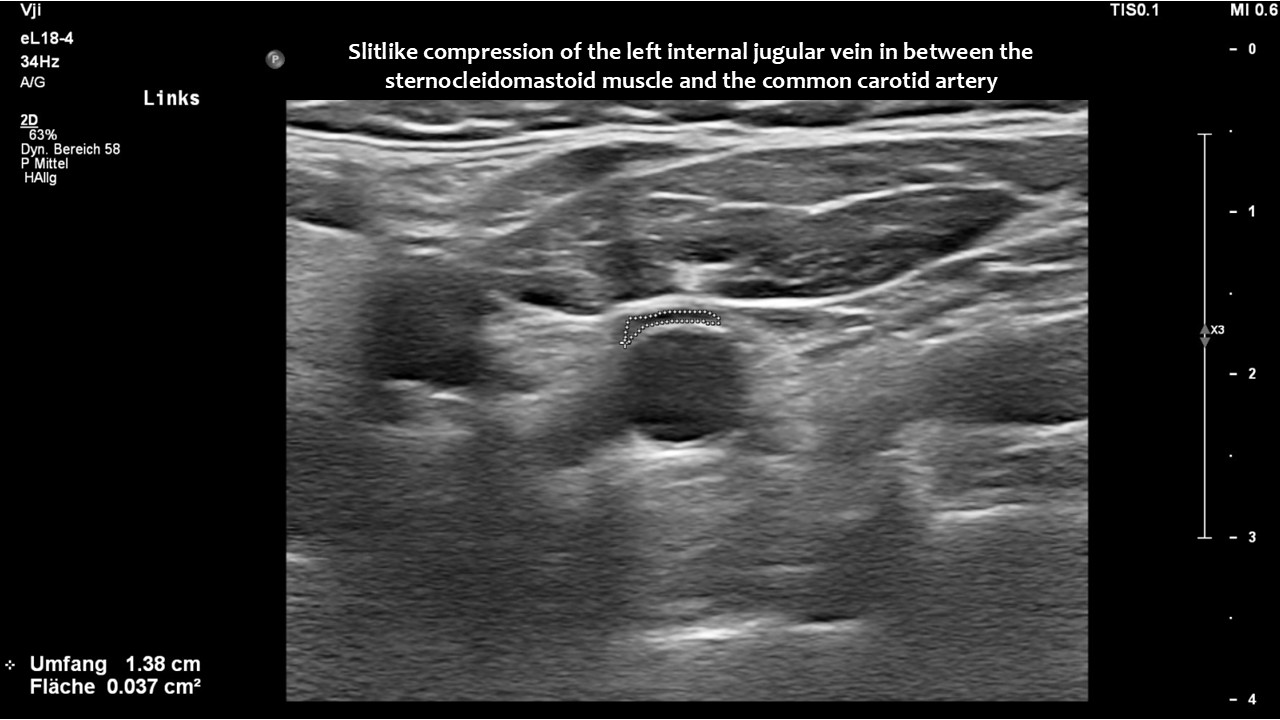

However, in this patient, both jugular veins were compressed. The middle portion of the internal jugular vein was pushed ventrally by the increased cervical lordosis on both sides, becoming squeezed between the carotid artery and the sternocleidomastoid muscle.

Consequently, blood had difficulty leaving the skull, resulting in continuously increased pressure and severe headaches, as well as other neurological dysfunction. The left side was more affected due to the double compression. This was clearly demonstrated by four-dimensional volume flow measurements in both jugular veins.

Only a four-dimensional volume flow measurement of the jugular veins can determine the cause of the daily headaches. The overall reduction in venous outflow from the brain in both jugular veins, totalling 258 mL/min, is significantly lower than the normal average volume of 719 mL/min. Consequently, the patient can eliminate only 36% of the required flow volume, while additional volume is forced into the skull from the left renal vein via the tronc réno-rachidien and from the left common iliac vein via the left ascending lumbar vein. This results in a chronic increase in intracranial pressure, as demonstrated by the elevated cerebrospinal fluid pressure obtained through a lumbar puncture. When the left jugular vein is also completely compressed due to increasing cervical lordosis when upright, the headaches become unbearable, accompanied by additional neurological symptoms as described by the patient.